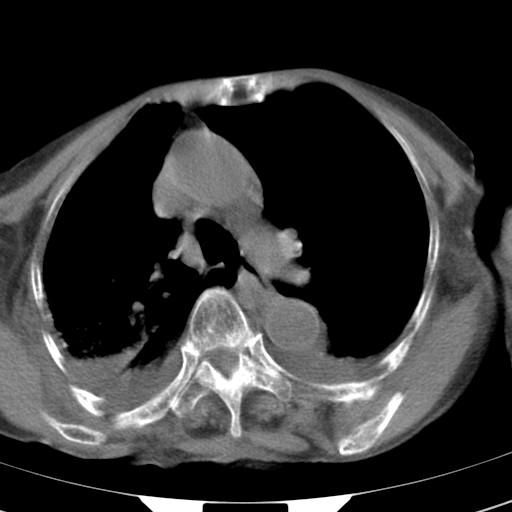

女,93岁,摔伤后检查。

右肺炎症,心功能不全伴双侧胸腔积液,右下肺膨胀不全,食管裂孔疝,冠脉钙化,心包少量积液,左侧肋骨骨折,请上传骨窗.

创伤性湿肺,双侧胸腔积液。可能有食管裂孔疝,进一步检查。骨折有无根据自己的机器及片子再仔细看吧。

右侧锁骨\\肩胛骨骨折、右侧湿肺,心功能不全伴双侧胸腔积液,右下肺膨胀不全,左膈破裂或食管裂孔疝,冠脉钙化,心包少量积液,请上传骨窗.

右肺炎症,心功能不全伴双侧胸腔积液,右下肺膨胀不全,食管裂孔疝,冠脉钙化,心包少量积液,左侧肋骨骨折,右肩甲骨粉碎性骨折。93岁,高寿哇!

右肺炎症,心功能不全伴双侧胸腔积液,右下肺膨胀不全,食管裂孔疝,冠脉钙化,心包少量积液,左侧肋骨骨折,右肩甲骨粉碎性骨折。